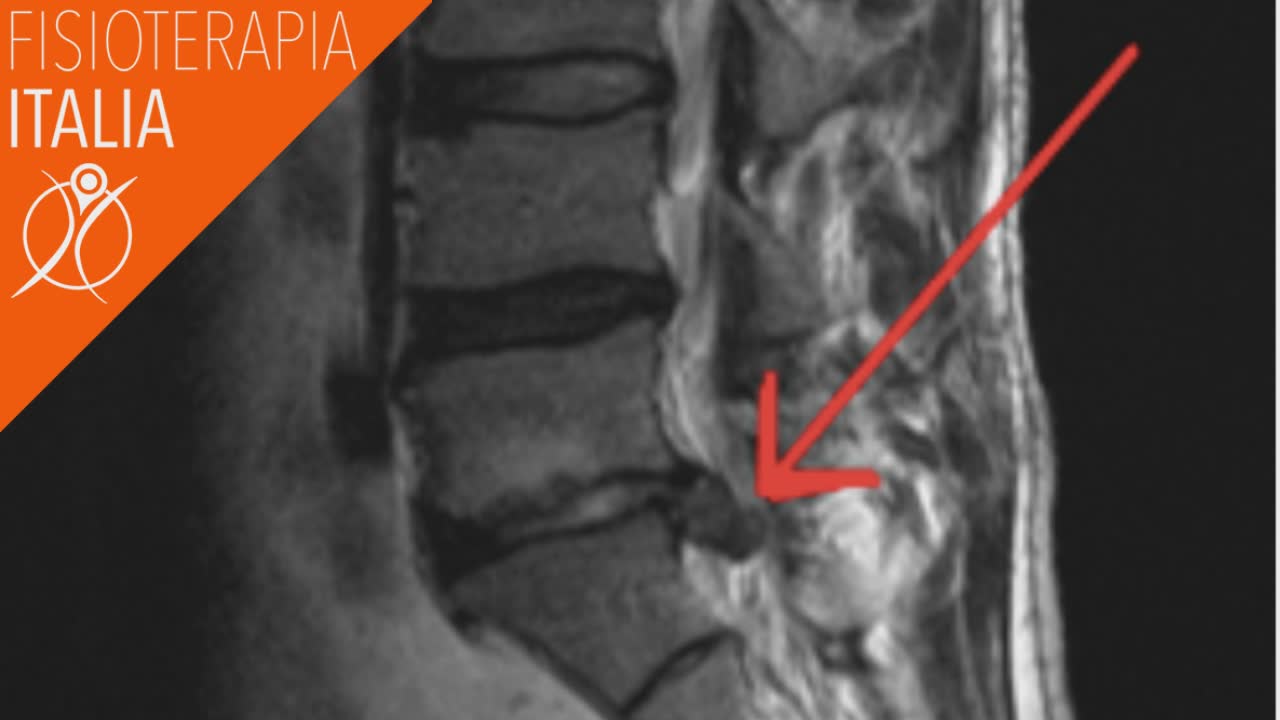

A volte gli esami strumentali sono richiesti in modo eccessivo, i raggi X e altri test, come la TAC, la risonanza magnetica e l'elettromiografia, vengono utilizzati per definire ulteriormente le cause esatte della sciatica ma non devono essere solo un supporto clinico. Infatti fare direttamente una risonanza magnetica quando si ha dolore potrebbe essere fuorviante. Molti problemi del disco sono spesso asintomatici.

Come si diagnostica una sciatalgia? In realtà la domanda giusta da porsi è: cosa sta causando la mia sciatica?

Gli specialisti e i fisioterapisti specializzati eseguono specifiche valutazioni. Partendo con l'anamnesi e poi eseguendo un esame fisico. I sintomi tipici descritti dal paziente, che risponde ad alcune domande e delle particolari manovre, aiutano l'operatore sanitario a diagnosticare la sciatica o meglio a capire l’origine dei sintomi.